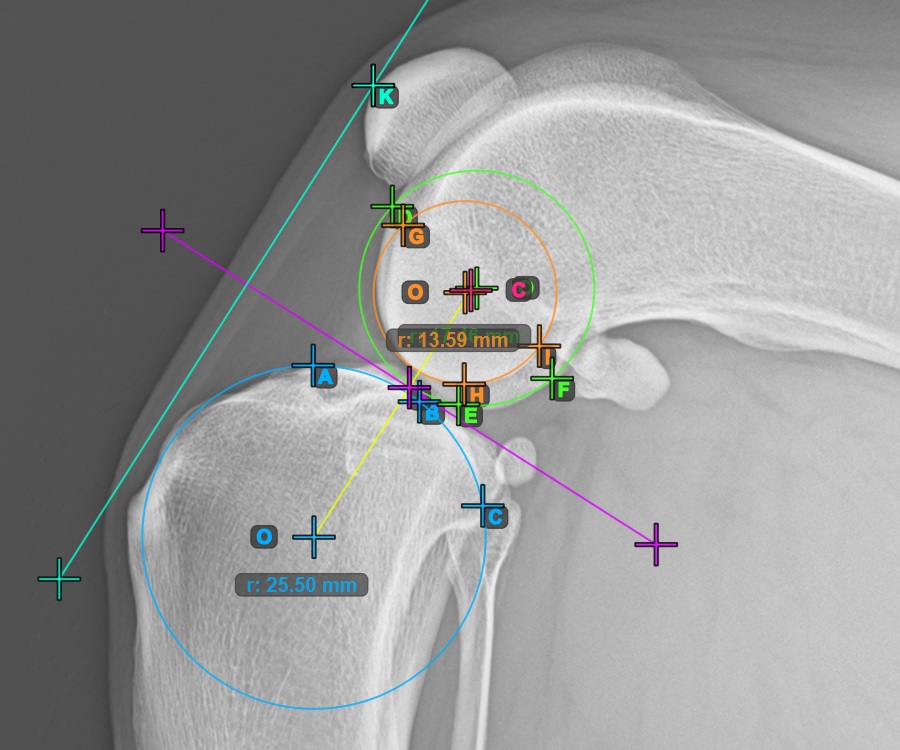

Mark the three points on the main condylus of the femoral bone (Condylus Femoris). Regardless of the order, make sure to mark the most cranial point, the most caudal point and the midpoint of the Condylus Femoris. A circle will be automatically constructed based on the three placed points.

The image below represents a typical placement of the three points on the first Condylus Femoris.